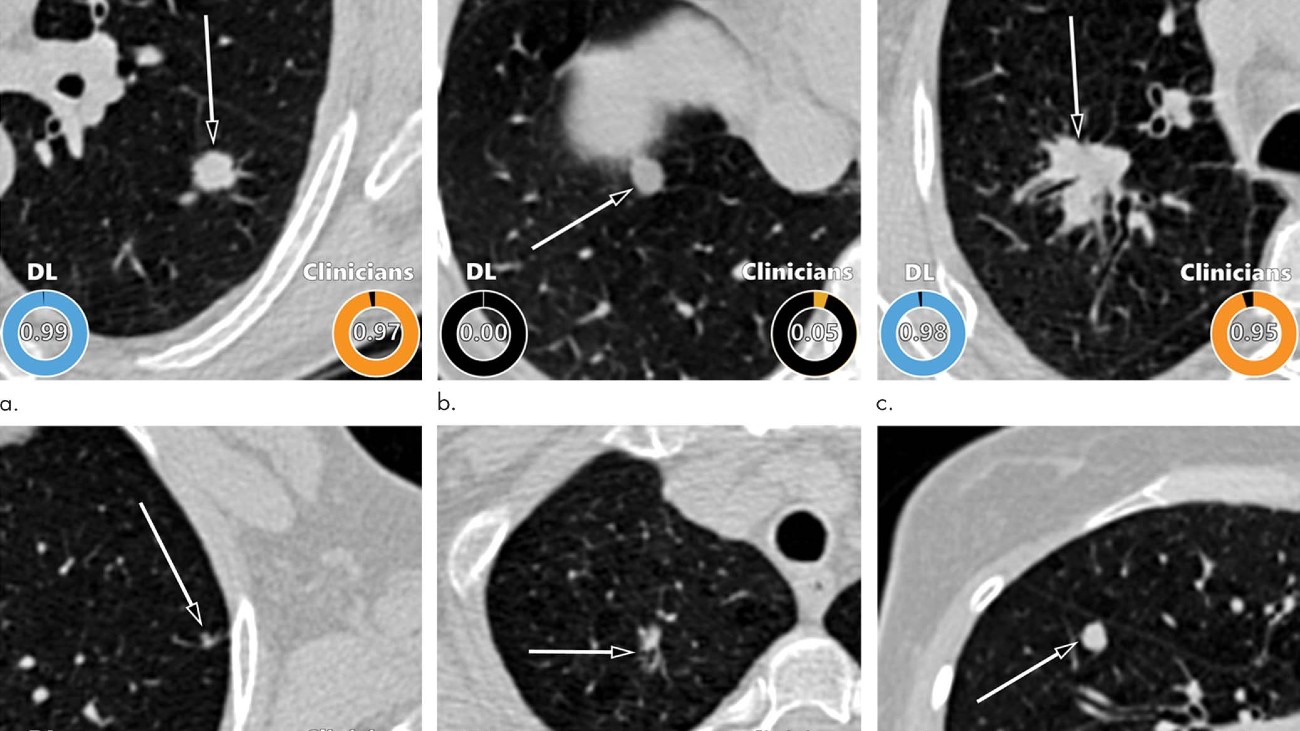

In een test vergeleken de onderzoekers de uitkomsten van het algoritme met het oordeel van vier thoraxradiologen, vijf radiologie-assistenten en twee longartsen. Daaruit bleek dat het kunstmatig intelligente systeem op hetzelfde niveau presteert als deze experts. In sommige gevallen wist het zelfs beter dan een specialist of een gezwel goed- of kwaadaardig was (zie onderstaande afbeelding).